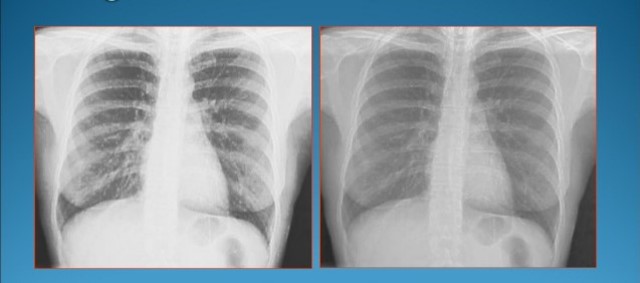

Primera Radiografia

La muñeca de la señora Röntgen. Primera imagen radiológica de la historia, tomada por Wilhelm Conrad Röntgen.